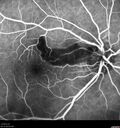

Severe diabetic tractional retinal detachment one year following diagnosis of type II Diabetes Mellitus245 views44 year old man The vision in the left eye started to decline about 4 days ago. Prior to that the left eye was the better eye. He was diagnosed with diabetes a year ago.Â

VA OD: Dcc20/50-1 OS: Dcc20/125-2, TP: OD:12 OS:13

Following two surgeries in each eye, silicone oil remaining forever, monthly anti-VEGF for severe DME - BCVA OU 20/200 at 3 yearsAug 17, 2022